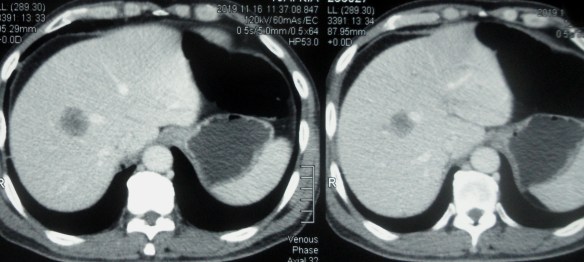

CT scan showed:

- An irregular mass in the distal segment of ascending colon, measuring 4.1 x 1 cm and it is 8.6 cm long. There is narrowing of the colonic lumen.

- There is pericolonic tumour infiltration and the lymph nodes are mildly enlarged.

- There are two small metastatic liver nodules measuring 1.3 cm and 1.4 cm.